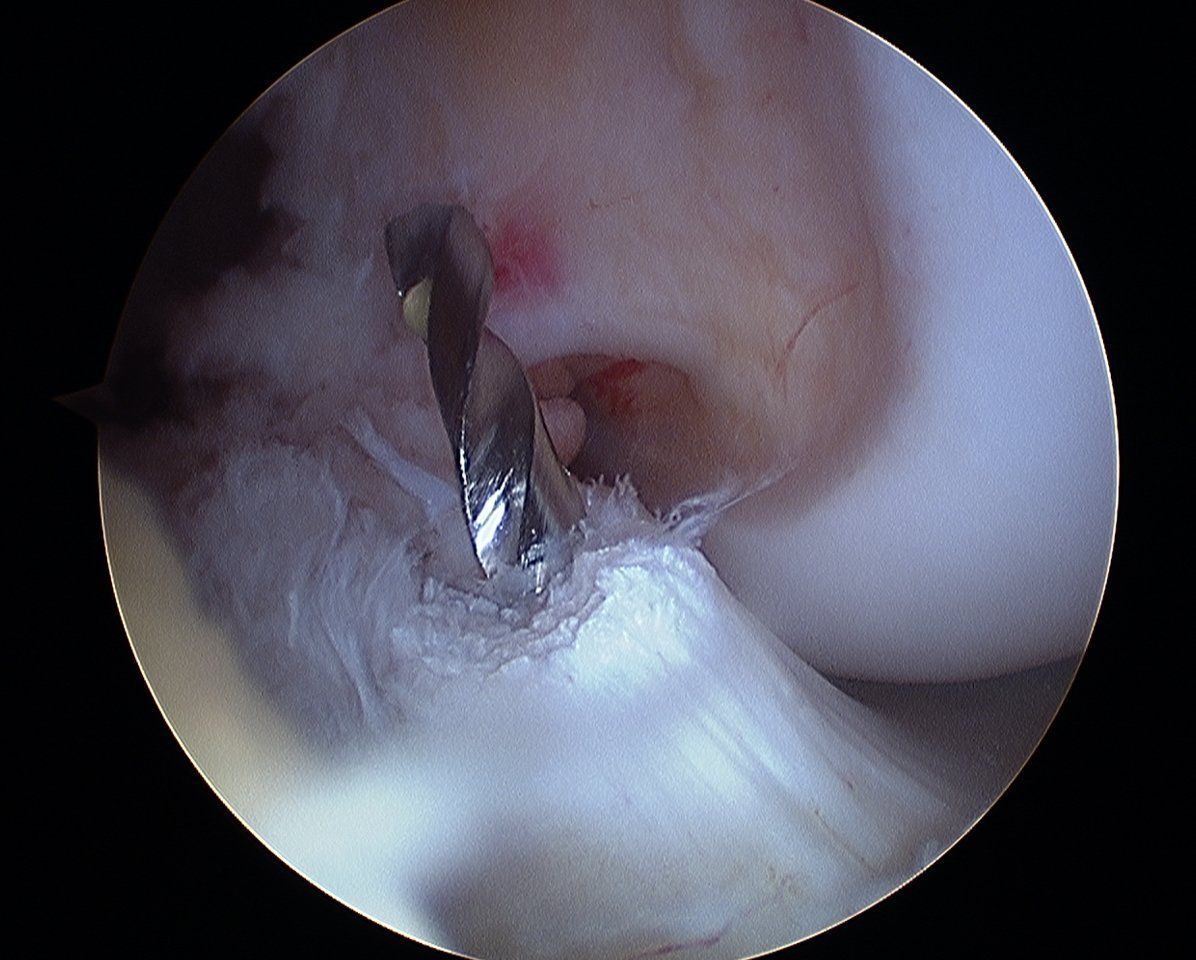

Les interventions couramment réalisées sont les arthroscopies de genou, les ligamentoplasties du ligament croisé antérieur, les ablations de matériel simples.